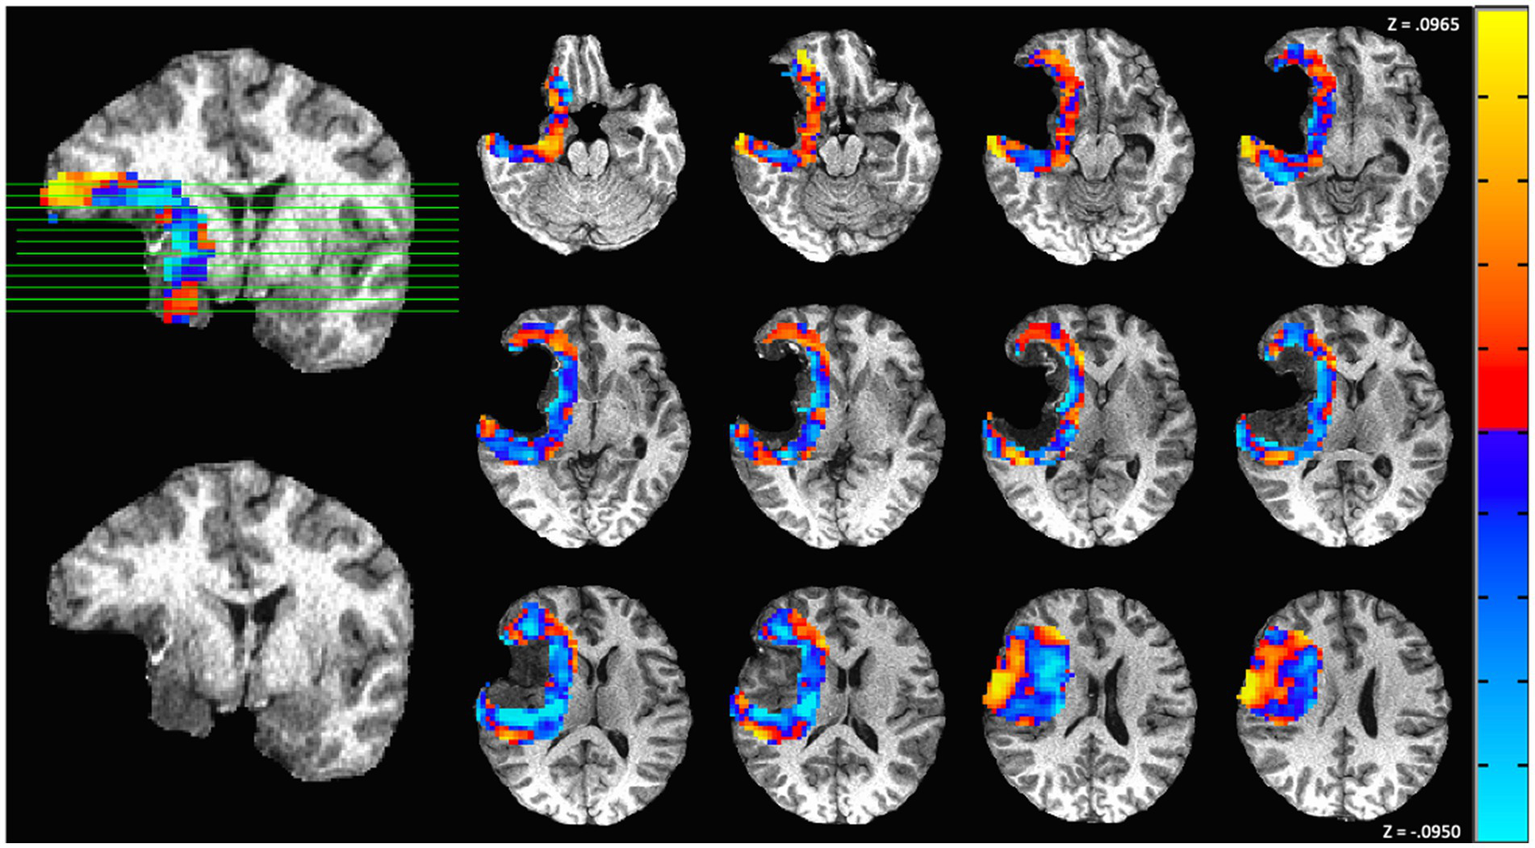

3.4 Representative case of sub-median survival

The above group results indicated that patients exhibiting largely decreased connectivity in the perilesional region had shorter survival time and more substantial declines in functional status than those exhibiting more neutral changes in perilesional connectivity. A representative subject with sub-medial survival is shown in Figure 5. The subject was a 60-year-old woman who underwent surgical resection of a Grade IV glioblastoma in the frontotemporal lobe. The subject’s preoperative KPS score was 60, and the immediate postoperative KPS score was 60. The connectivity map of postsurgical scans shows an overall decrease in connectivity in the perilesional area relative to the contralesional regions, suggesting a status of weakened connections at the postsurgical time point. This subject survived for under 3 months from diagnosis. At 6 months postoperative, however, the subject was deceased, leading to a KPS score of zero. In this case, the perilesional connectivity of below-zero values suggested a prediction of sub-median survival.

Figure 5

Functional connectivity map from one representative subject with left frontotemporal World Health Organization (WHO) grade IV glioblastoma. In these images, red represents an increase in functional connectivity of the perilesional region compared to the corresponding contralateral region, and blue represents a relative decrease. This patient is a representative example of primarily decreased connectivity. Before surgery, the patient presented a Karnofsky Performance Status (KPS) score of 60. However, the patient did not survive to the 6-month postsurgery benchmark, indicating a KPS change of −60.